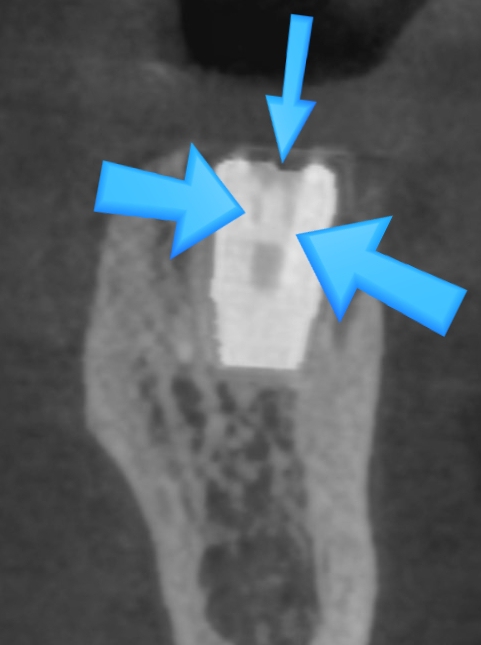

다른치과 임프란트 스크류 파절상태

왼쪽은 위의 파노라마 실제환자 사진이고 오른쪽은 참고사진입니다.

참고 사진을 보면 중간에 나사가 있습니다.

위의 환자는 윗부분 지대주와 아래 픽스쳐를 연결시키는 스크류(나사)가 부러져서

머리부분이 흔들릴 수 밖에 없는 것이었습니다.

나사가 박혀있기 때문에 기존 임플란트를 재사용하기는 힘들었고

기존 임플란트도 제거하였습니다.